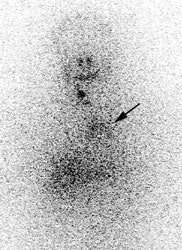

False negative I-123 diagnostic scan: The patient shown below had undergone thyroidectomy for papillary thyroid cancer and had a known metastasis to the left iliac bone. A diagnostic I-123 scan was performed to evaluate for extent of disease (posterior whole body image on left). The I-123 scan demonstrated neck bed uptake, but the iliac metastasis was not identified. Despite the negative diagnostic study, the patient received high dose I-131 therapy. The post therapy I-131 scan clearly revealed the iliac bone lesion (black arrow). |